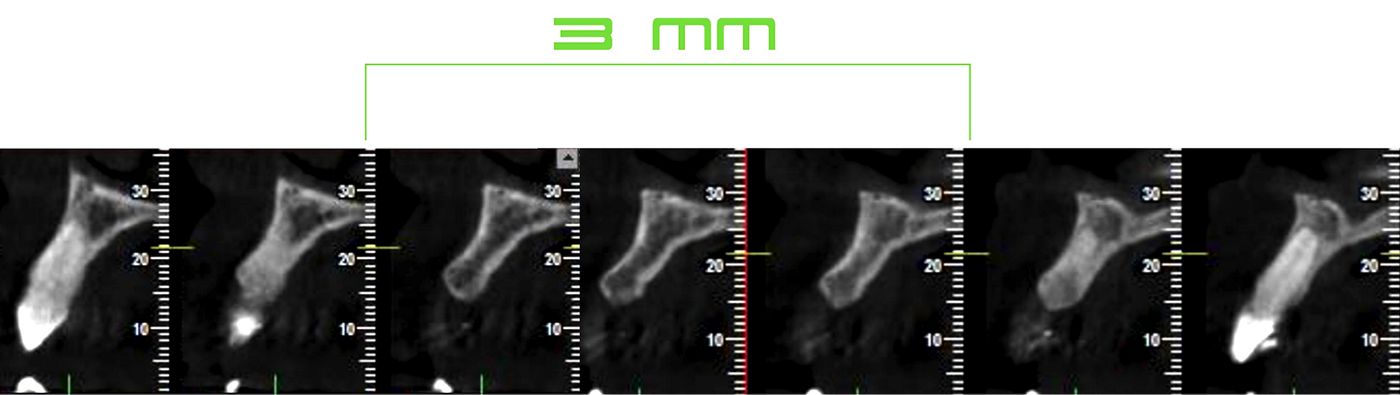

After an assessment of periapical radiography (Fig. 6), cone beam computed tomography (Fig. 7-8) and a clinical evaluation of tooth 12, it was decided that a Straumann® BLT Ø 2.9 mm was a good solution for this clinical case due to the narrow interdental space and limited horizontal bone available (5.25 mm).